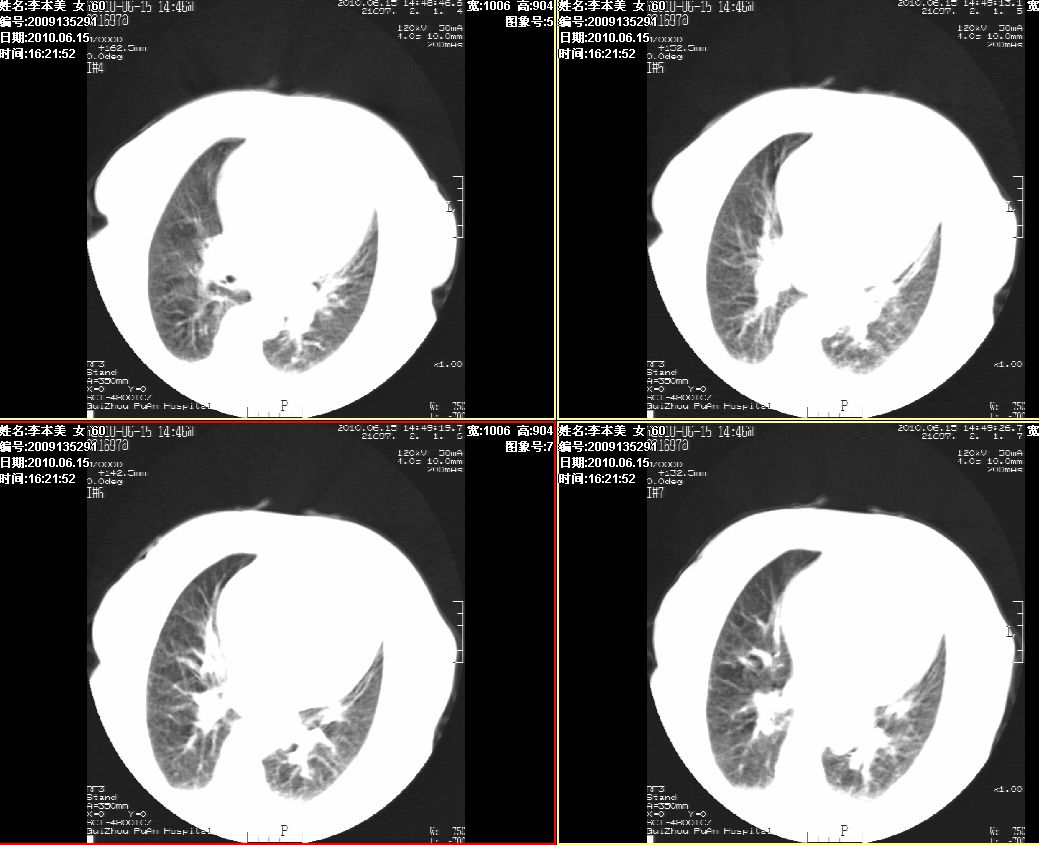

李某,60岁,女,胸闷气促一月,照片发现心后缘圆形高密度影,ct扫描如下。请大家看看,描述一下,给个诊断意见。

图像欠清,主动脉瘤?食管肿瘤?食管裂孔疝?建议增强。

主动脉瘤?食管肿瘤?食管裂孔疝?建议增强。